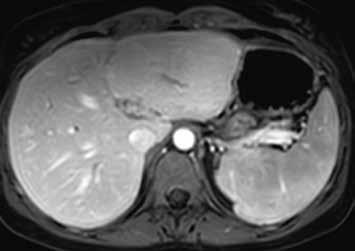

Již nativně jsou na T1-váženém obraze vidět vícečetná hyperintenzní ložiska (7). V arteriální fázi ložiska zůstávají hyperintenzní (8), v portovenózní fázi (9) a v hepatospecifické fázi (10) postupně splývají s okolním parenchymem.

Nativně je v jaterním parenchymu naznačeno několik minimálně hyperintenzních ložisek (13). Ložiska se zvýrazňují ve fázi arteriální (14) i portovenózní (15). V hepatospecifické fázi jsou nadále hyperintenzní (16).